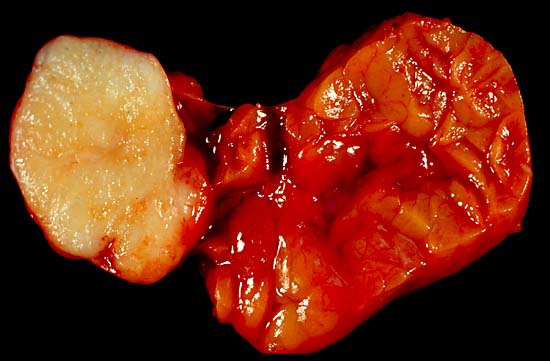

침샘암은 침샘에 발생하는 종양으로, 덩어리나 부기를 동반하며, 초기에는 양성 종양과 구별이 어려울 수 있다. 진단은 신체 검사, 내시경, MRI 또는 CT 스캔, 생검 등을 통해 이루어진다. 치료는 수술이 주를 이루며, 방사선 치료, 화학 요법, 표적 치료가 사용될 수 있다. 침샘 종양의 대부분은 양성이며, 발생률은 드문 편이다.

침샘암은 주로 영향을 받은 침샘에 덩어리나 부기 형태로 나타나며, 이는 오랫동안 있었을 수도 있고 없었을 수도 있다. 덩어리는 구강건조증과 같은 침샘관 막힘 증상을 동반할 수 있다. 보통 초기 단계에서는 양성 종양과 악성 종양을 구별하기 어렵다. 악성 종양의 주요 특징 중 하나는 신경 침범이다. 예를 들어 안면 신경 손상 징후(예: 안면 마비)는 악성 이하선 종양과 관련이 깊다. 안면 통증과 감각 이상 또한 악성 종양과 매우 자주 연관된다.[28] 악성 종양을 암시하며 추가 검사가 필요한 다른 위험 신호로는 덩어리가 피부에 고정되거나, 점막에 궤양이 생기거나, 딱딱해지는 것 등이 있다.[29]